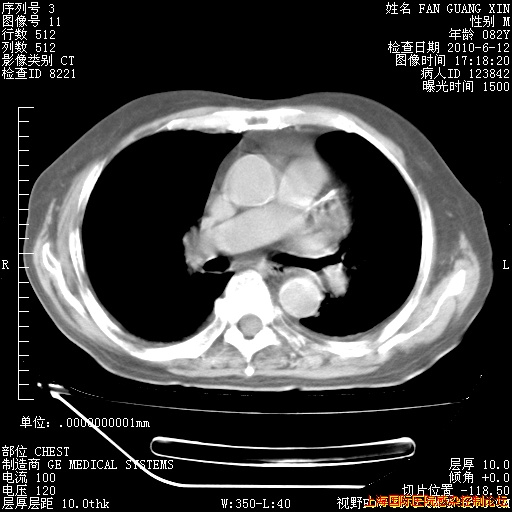

补发6月12日肺部CT肺窗

6月12日肺窗

6月12日纵膈窗